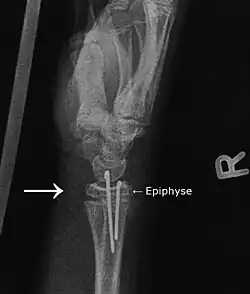

Osteosynthese is een techniek waarbij twee of meer botdelen aan elkaar worden vastgezet. Dit kan met behulp van pennen, schroeven en platen. Hiermee wordt getracht om de botdelen in de juiste positie ten opzichte van elkaar te plaatsen en met een zo klein mogelijke ruimte ertussen. De uiteindelijke genezing van de fractuur wordt niet versneld.[1]